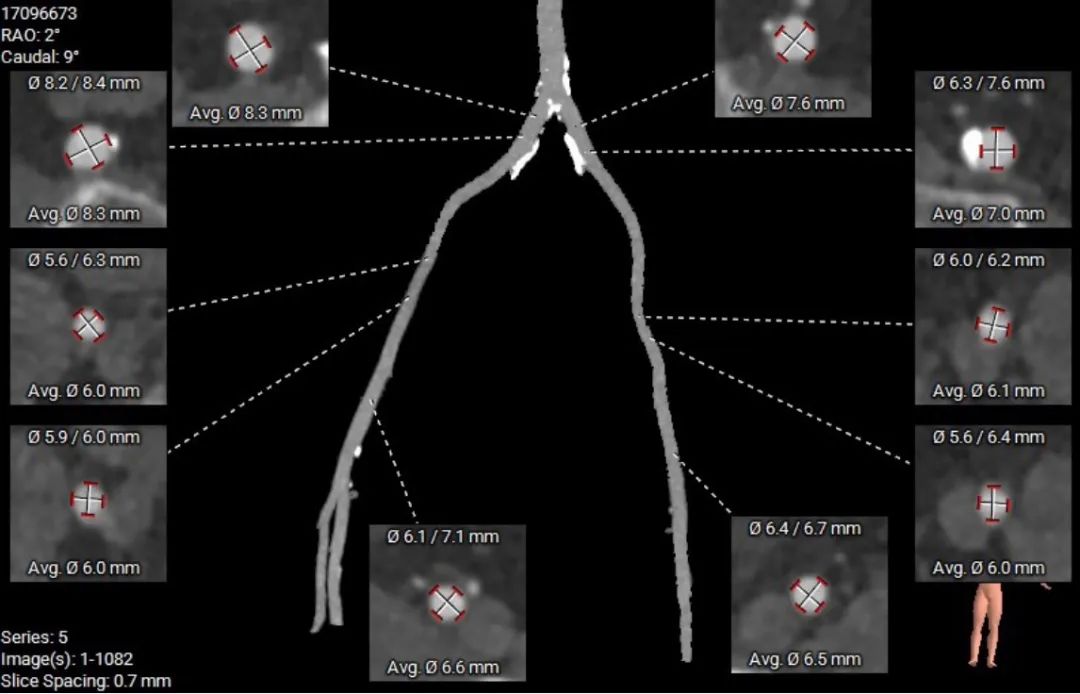

外周血管及主动脉弓解剖

股动脉入路无迂曲,分叉高度可。髂总、腹主钙化分布。左侧血管平均最小内径6.0mm, 右侧血管平均最小内径6.0mm。

建议右侧股动脉为主入路,穿刺点附近少量钙化分布,建议避开钙化穿刺。

股动脉入路无迂曲,分叉高度可。髂总、腹主钙化分布。左侧血管平均最小内径5.4mm, 右侧血管平均最小内径6.2mm。

建议右侧为主入路,穿刺点附近钙化夹层,建议外科切开。左右髂总钙化,内径较小,建议18F大鞘预扩。